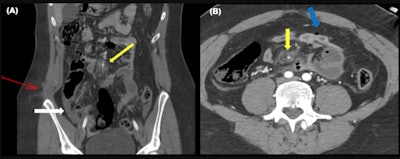

In motor vehicle collisions bowel injuries are more likely to be ischemic than in other blunt trauma or penetrating trauma, the researchers continued.

"They occur because of shearing forces at the junction of mobile and fixed bowel plus the high intraabdominal pressure caused by the entrapment of intestine loops over and above the lap belt," they pointed out. "These mechanisms can cause a bucket-handle tear which is an injury in which the mesentery avulses off a bowel loop. Mesenteric injury can be misdiagnosed first causing a delay in surgical intervention."

These kinds of ischemic injuries are more frequent in the ileocecal region and proximal jejunum. In the Madrid facility's database, the small intestine was damaged more frequently than the colon.

The most specific CT signs are bowel mural discontinuity, pneumoperitoneum, or active mesenteric bleeding.

"Free oral contrast is considered by some authors as the most specific sign of blunt trauma of the bowel and mesentery," they wrote. "Nevertheless, a retrospective single-center study found that hyperenhancement of the bowel adjacent to a hypoenhancing segment would be the most specific sign in a routine trauma CT exam."

Free fluid or interloop fluid, bowel wall thickening, or mesenteric contusions are relatively less specific signs, but they are more prevalent, according to the authors.